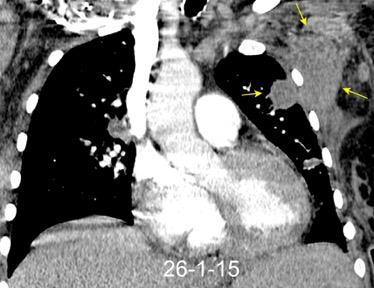

Masa axilar izquierda y derrame pleural derecho. Implantes pleurales, paraespinales . Ganglios en mamaria interna. Linfoma B difuso

Jaffe ES. Diagnosis and Classification of Lymphoma: Impact of Technical Advances.

2005. Masa pulmonar.

Linfoma NH de cél. B. Invasión Transtorácica.

Afectación axilar